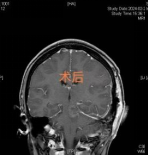

术后复查:病灶完整切除

各项复查显示,病灶已被完整切除、颅神经功能均未受损。陈女士右侧肢体感觉和运动功能得到明显改善,她阴郁的脸上终于露出了久违的笑容。